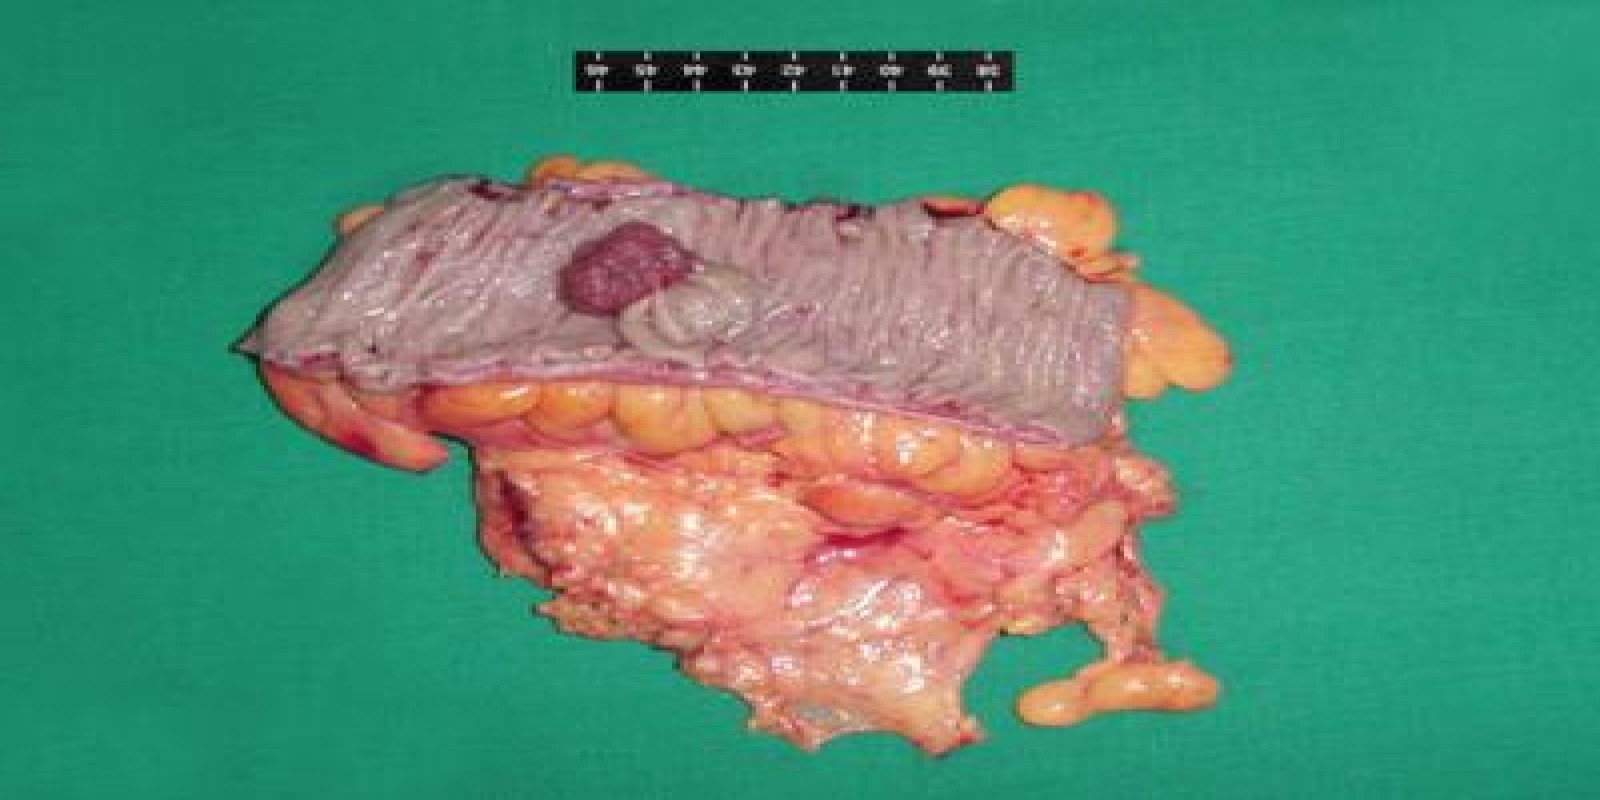

Caso Código 126B de Pólipos do Cólon

Cod.: 126B